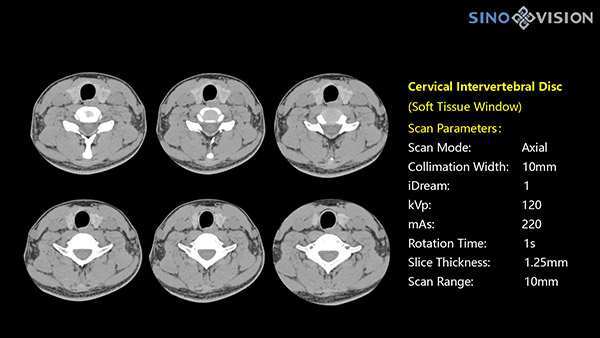

Инновационный 128-срезовый компьютерный томограф SinoVision InsitumCT 568 – это сочетание высокой скорости работы, низкой дозы и максимума возможностей для подавляющего большинства клинических случаев, как в рутинных, так и в углубленных специализированных исследованиях, в том числе педиатрические и кардиологические исследования при сверхнизких дозах.

РМК

Полнофункциональный 128-резовый компьютерный томограф InsitumCT 568 - это лучшее в новом поколении широкодиапазонных томографов с 128 срезами и большой диафрагмой. Этот КТ-сканер с большой апертурой обеспечивает 128 срезов КТ с диафрагмой 76 см, улучшает разрешение изображения до 21Lp/cm, помогает точно диагностировать и лечить заболевания, а также значительно улучшает клинические характеристики и расширяемость оборудования. Позволяет реализовать визуализацию в высоком разрешении и в малых дозах лучевой нагрузки.

Полнофункциональная платформа клинической диагностики может точно определять местонахождение и диагностировать общие повреждения качественно и количественно, а также достигать полнофункциональных клинических показателей, включая обширные кардиологические исследования со сверхнизкими дозами лучевой нагрузки.

Компьютерный томограф InsitumCT 568 имеет ряд инновационных технологий, позволяющих значительно снизить лучевую нагрузку на пациента:

- Функции V-beam и iDream оптимизируют дозу в реальном времени, позволяя снизить ее до 63% при сохранении максимального качества изображения.

- Снижение лучевой нагрузки: До 63% % (опции iDeam, V-beam)

- Разрешение: 21 Lp/cm